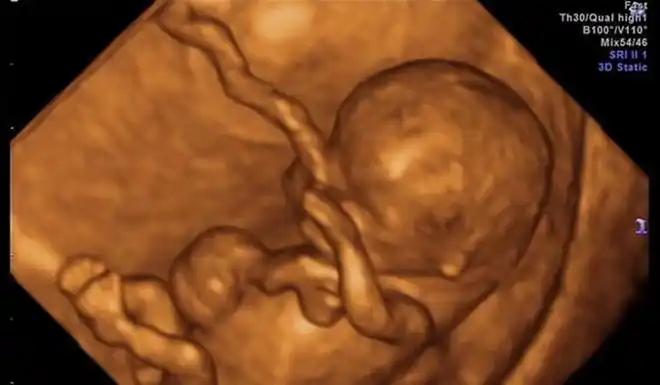

孕妈做b超发现娃嘴歪了,医生安慰说正常,宝宝出生后妈妈被丑哭

为什么胎儿四维照"丑相"?b超医生告诉你真相,原因是这三点